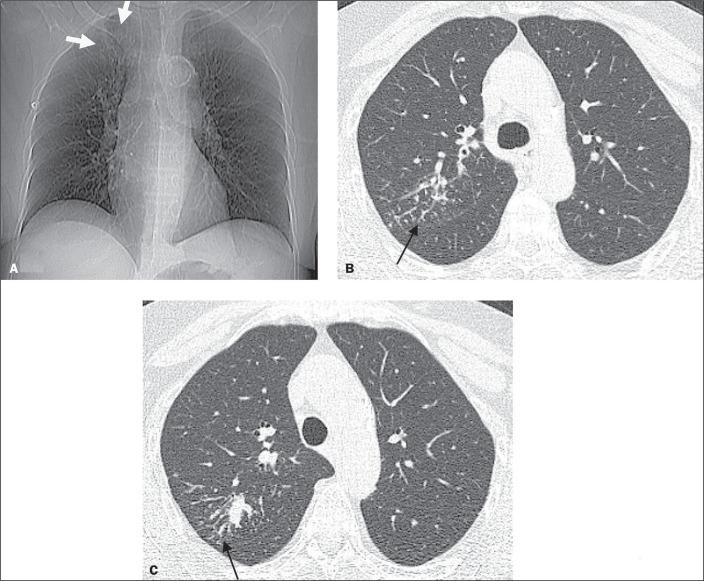

肾移植受者活动性肺结核的放射学表现:4例回顾性研究及文献复习

Radiological presentation of active pulmonary tuberculosis in kidney transplant recipients: a retrospective study of four cases and a review of the literature.

Although kidney transplantation is the best therapeutic option for patients with chronic kidney disease, the immunosuppression required greatly increases susceptibility to infections that are responsible for high post-transplant mortality. Pulmonary tuberculosis (TB) represents a major cause of such infections, and its early diagnosis is therefore quite important. In view of that, we researched the manifestations of active pulmonary TB in kidney transplant recipients, through chest X-ray and computed tomography (CT), as well as determining the number of cases of active pulmonary TB occurring over a 3.5-year period at our institution. We identified four cases of active pulmonary TB in kidney transplant recipients. The CT scans provided information complementary to the chest X-ray findings in all four of those cases. We compared our CT findings with those reported in the literature. We analyzed our experience in conjunction with an extensive review of the literature that was nevertheless limited because few studies have been carried out in lowand middle-income countries, where the incidence of TB is higher.

尽管肾移植是慢性肾病患者的最佳治疗选择,但所需的免疫抑制会大大增加感染易感性,而感染是移植后高死亡率的原因。肺结核(TB)是此类感染的主要原因,因此其早期诊断非常重要。有鉴于此,我们通过胸部X光和计算机断层扫描(CT)研究了肾移植受者活动性肺结核的表现,并确定了我院3.5年期间发生的活动性肺结核病例数。我们在肾移植受者中发现了4例活动性肺结核病例。在所有这4例病例中,CT扫描提供了与胸部X光检查结果互补的信息。我们将我们的CT检查结果与文献报道的结果进行了比较。我们结合对文献的广泛回顾分析了我们的经验,不过文献回顾有限,因为在结核病发病率较高的低收入和中等收入国家开展的研究很少。